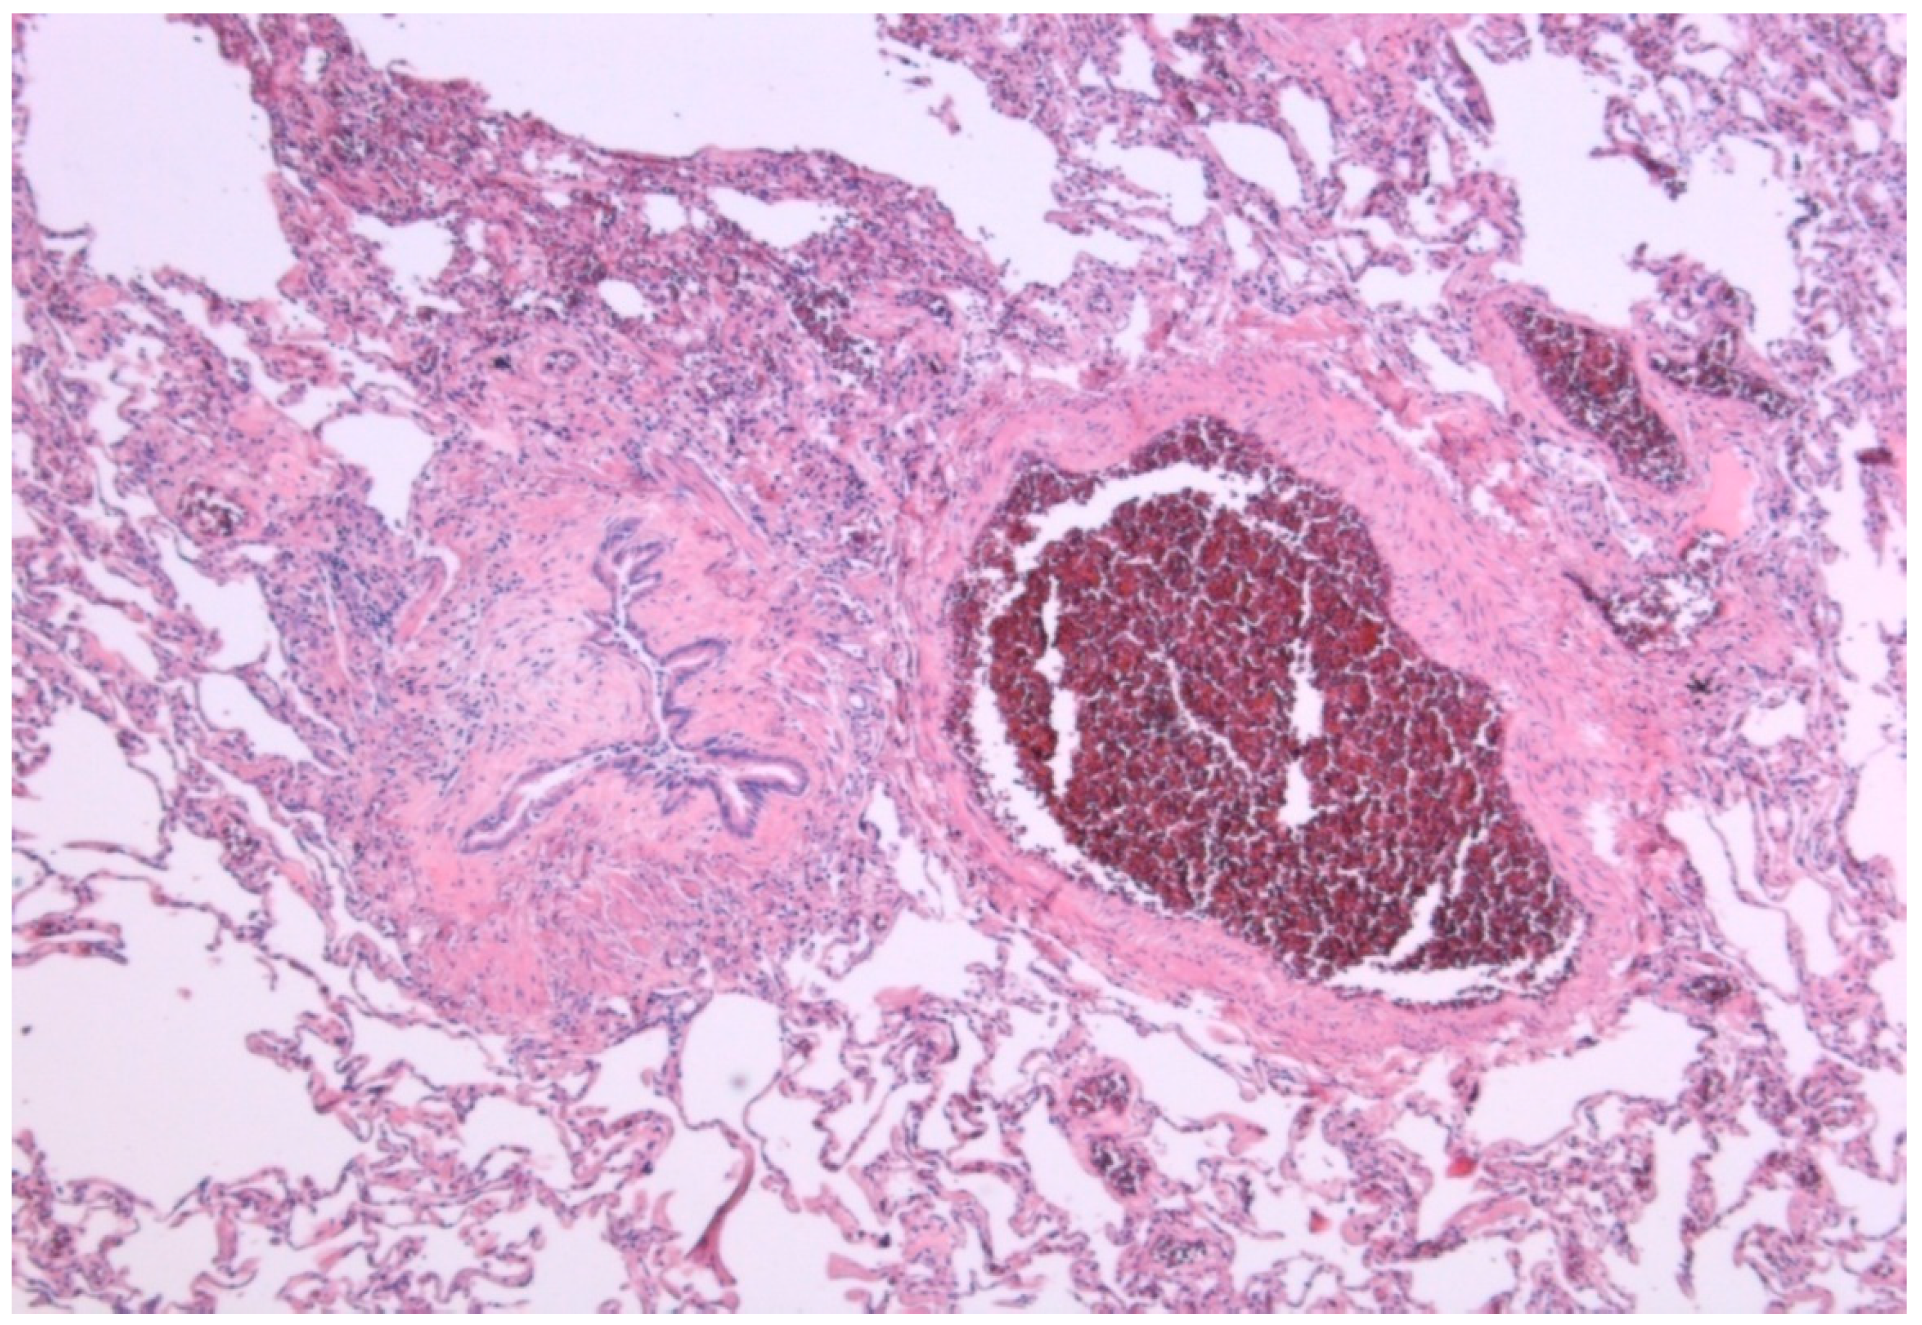

| Histopathologic diagnosis of UIP or fibrotic NSIP |